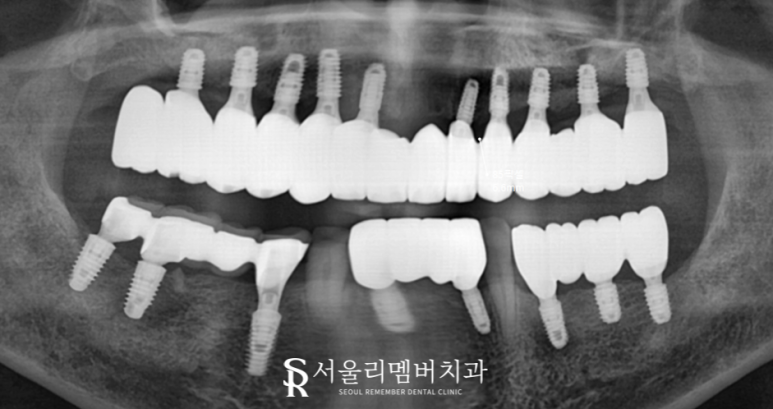

최종 보철은 치아의 기능과 외관을 모두 살려줘야 되기 때문에 제작 시 고려해야 될 것들이 많습니다.

형태와 색조가 주변 인접치들과 잘 어우러질 수 있도록 조화롭게 만들어줘야 되죠.

물론 여기에 잃어버린 교합을 완성시켜 줄 수 있도록 기능적인 면도 더해져야 됩니다.

서울대입구역 치과 에서는 위 내용들을 모두 고려하여 보철 제작을 마쳤는데요.

보철 들뜸이 일어나고 잇몸 건강이 좋지 않았던 전과는 달리

환자께 딱 맞는 맞춤 임플란트가 완성이 되었네요.

무엇보다 식사 시 느낄 즐거움이 크실 텐데요.

오래오래 관리를 잘 하셔서 이 즐거움을 잃지 않고 쭉- 느끼셨으면.. 하는 바람입니다.